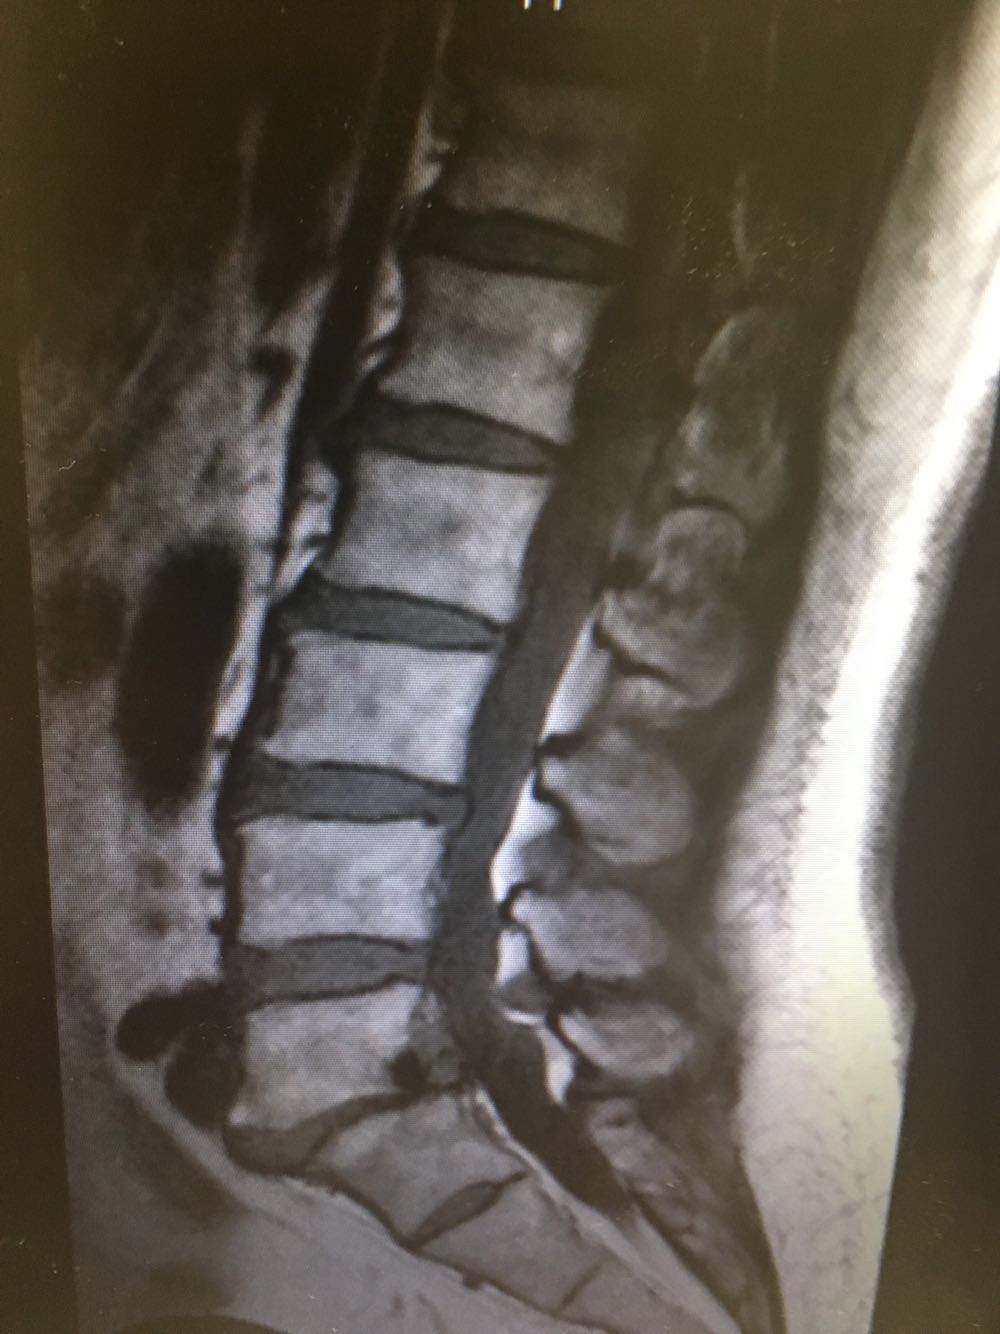

患者,女性,60岁 主诉:腰痛伴下肢疼痛2年 现病史:患者于2年前无明显诱因下出现腰痛伴左侧下肢疼痛,休息后缓解,未予重视,半年前出现双下肢外侧疼痛,酸胀伴跛行,休息后稍缓解,病程中否认头晕头痛、恶心呕吐等不适,遂至我院门诊就诊,查腰椎X片示:L5椎体向前轻度滑脱,伴退行性变,椎间隙变窄,现为进一步诊治收治入院,发病以来,神清,精神可,胃纳夜眠可,二便无殊,体重无明显变化。

查体:脊柱无侧弯畸形,下肢肌力肌张力正常,下肢反射均正常。 辅检:腰椎MRI